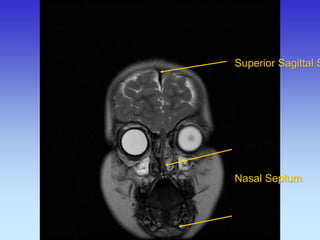

Superior Sagittal Sinus

Superior Sagittal Sinus Nasal Septum

Eye Ball